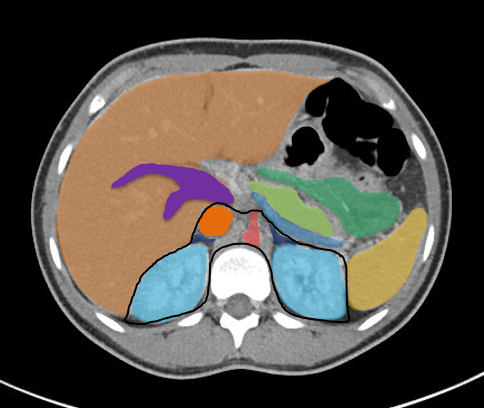

Inteventionelle Radiologie-Teil der Diagnostischen Radiologie oder ein eigenständiges Fachgebiet?

Die Entwicklung und Integration der interventionellen Radiologie im klinischen Alltag wird weltweit unterschiedlich gehandhabt. Während sie in den USA bereits als eigenständiges Fachgebiet anerkannt ist, gilt sie in Deutschland nach wie vor als fakultatives Teilgebiet innerhalb der Radiologie.

In der interventionellen Radiologie beschränkt sich die Tätigkeit des Radiologen nicht allein auf die bildgebende Diagnostik. Vielmehr übernimmt er eigenständig minimalinvasive Eingriffe und trägt dabei die Verantwortung für die prä-, peri- und postoperative Versorgung der Patient: innen.

Mit diesem Wahlfach möchten wir Ihnen praxisnahe Einblicke in das vielseitige und verantwortungsvolle ärztliche Arbeiten in der interventionellen Radiologie ermöglichen.